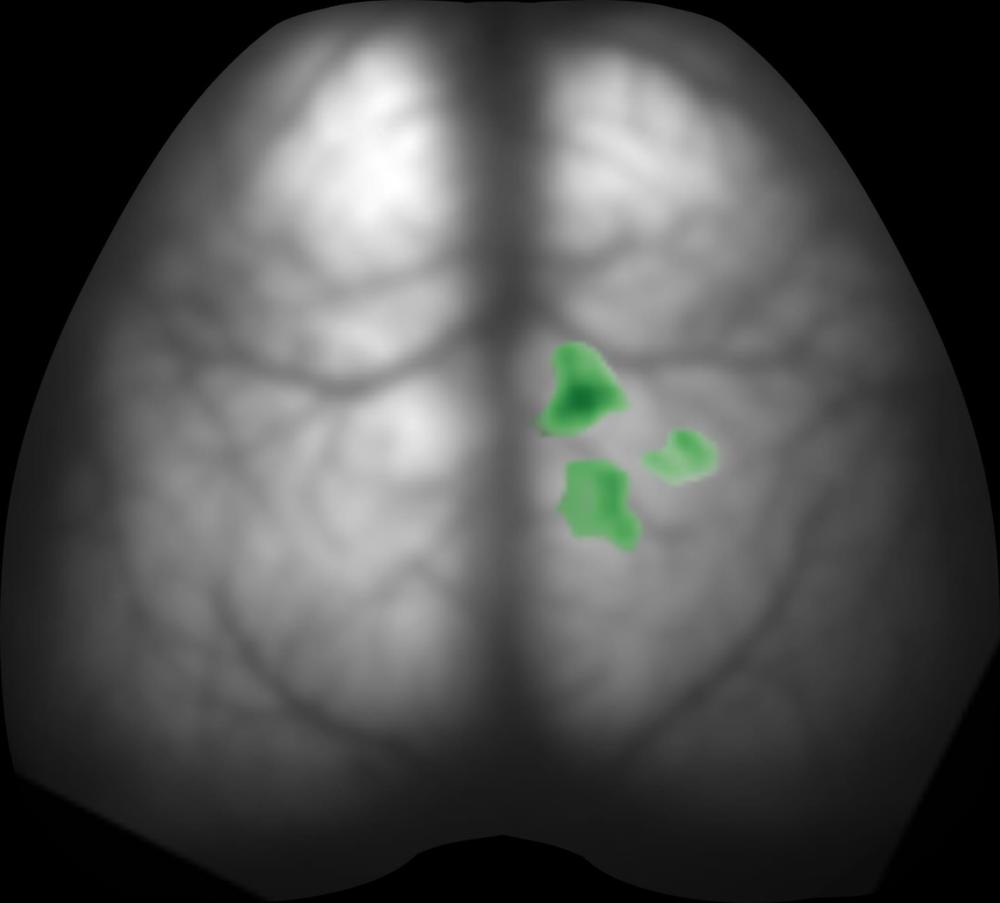

A new study provides the first visual evidence showing that brain circuits in living animals can be activated by ultrasound waves projected into specific patterns (holograms).

As neurons in the hologram-focused regions became activated, they generated a fluorescence signal that the camera recorded, enabling the researchers to measure to the degree to which different brain regions were activated in response to TUS.